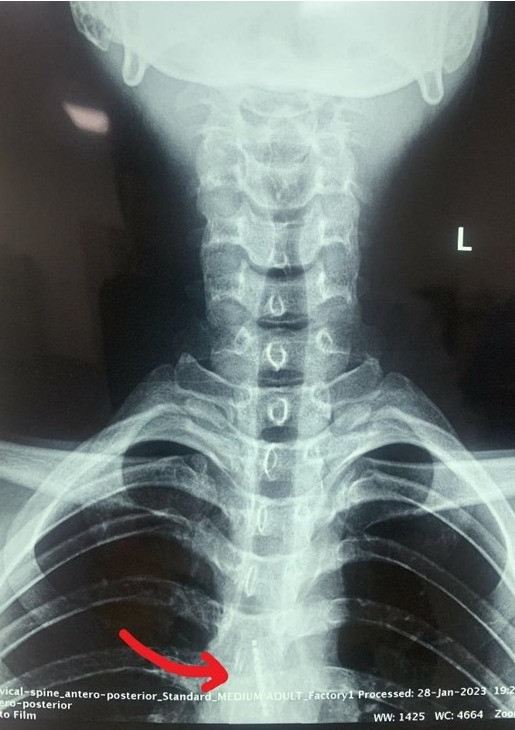

Bệnh nhân được đưa đi cấp cứu tại Khoa Tai - Mũi - Họng, Bệnh viện Quân y 103 (Hà Nội) trong tình trạng đau tức vùng ngực. Bác sĩ khám nội soi tai - mũi- họng, chụp phim X-quang để chẩn đoán, phát hiện dị vật cản quang thực quản đoạn ngực - bụng.

Do dị vật khá lớn là bàn chải đánh răng, nằm sâu ở thực quản đoạn ngực- bụng nên bệnh nhân đã được gây mê, đặt ống cứng soi trực tiếp thực quản lấy dị vật. Sau thủ thuật, bệnh nhân ổn định, được đặt sonde dạ dày nuôi dưỡng, xuất viện sau 3 ngày theo dõi và điều trị.